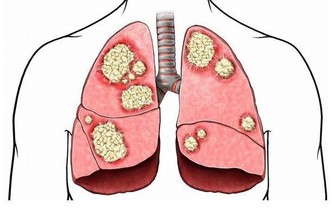

放屁這個事情很多人都覺得不文雅,又有怪聲又有異味,公共場合難免尷尬,但是屁又是非存在不可的東西,但是,如果放屁太多,也說明你的身體健康出現了問題。 屁的原材料是與我們的唾液或食物一起嚥下去的空氣,其中有一部分以打嗝的方式從胃排出,剩下的空氣則進入腸部,成為屁的主要來源。空氣的主要成分是氮和氧。胃部的空氣進入腸道,裡面的氧就會被吸收,剩下的氮,則原封不動地成為屁的主要成分之一。人為什麼會放屁呢?一是人自身吞下的空氣;二是胃腸道內產生的氣體;三是由血液滲透而入的氣體。這些氣體,一部分由血液吸收再經肺排放,其餘的就是以放屁的方式從肛門中排出體外。 (圖片翻攝自yidianzixun) 這些氣體的主要成分,包括氧、氮、氫、二氧化碳和甲烷。氮是沒有任何味兒的,更不會發臭,如果屁發出臭味,是身體內部的問題,那都是由於腸道腐敗造成的。主要是由吲哚、硫化氫等所導致,就是在人體消化的過程中,食物經胃消化後,將殘渣送到大腸,經細菌作用而分解成大便時,這時氣體就被污染,於是從肛門中排出臭屁。